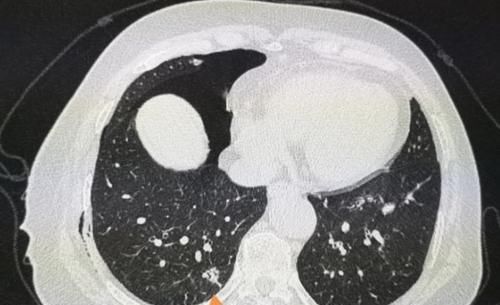

我们观察她的CT片,在她的右肺下叶有一个肺大泡(黄色箭头),紧挨着胸膜,由于气流冲击被顶破了,肺里的气体进入胸腔发生气胸。

这种少量气胸并不严重,保守观察就好,会慢慢吸收。

但我们同时又有一个意外的发现:橙色箭头是一个肺结节,

文章插图

结节外侧有胸膜牵拉,内部可以看到支气管充气征,综合分析符合一个高分化腺癌的CT表现。

这个小肿瘤没有症状,可以通过胸腔镜微创切除,手术后5年生存率接近100%。

但如果没有这个气胸发作,拖个一年半载的,等出现肺部症状再来,就不好说了。